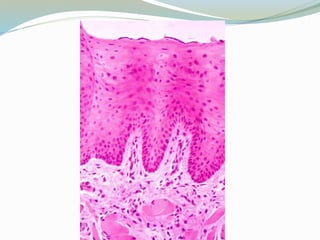

Esófago

 EPITELIO: Plano estrtificado no queratinizado, en la

parte inferior presenta una transición repentina a

epitelio cilíndrico